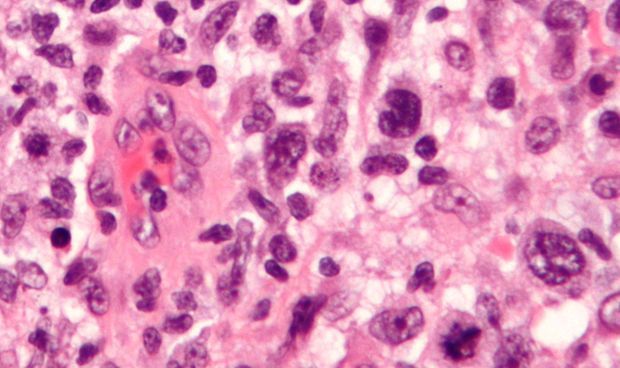

Imagen de células cancerosas de un linfoma.